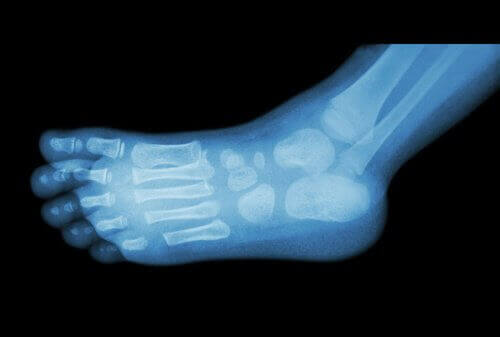

Doktorlar topuk dikenlerini basit bir x-ray ile teşhis edebilirler.